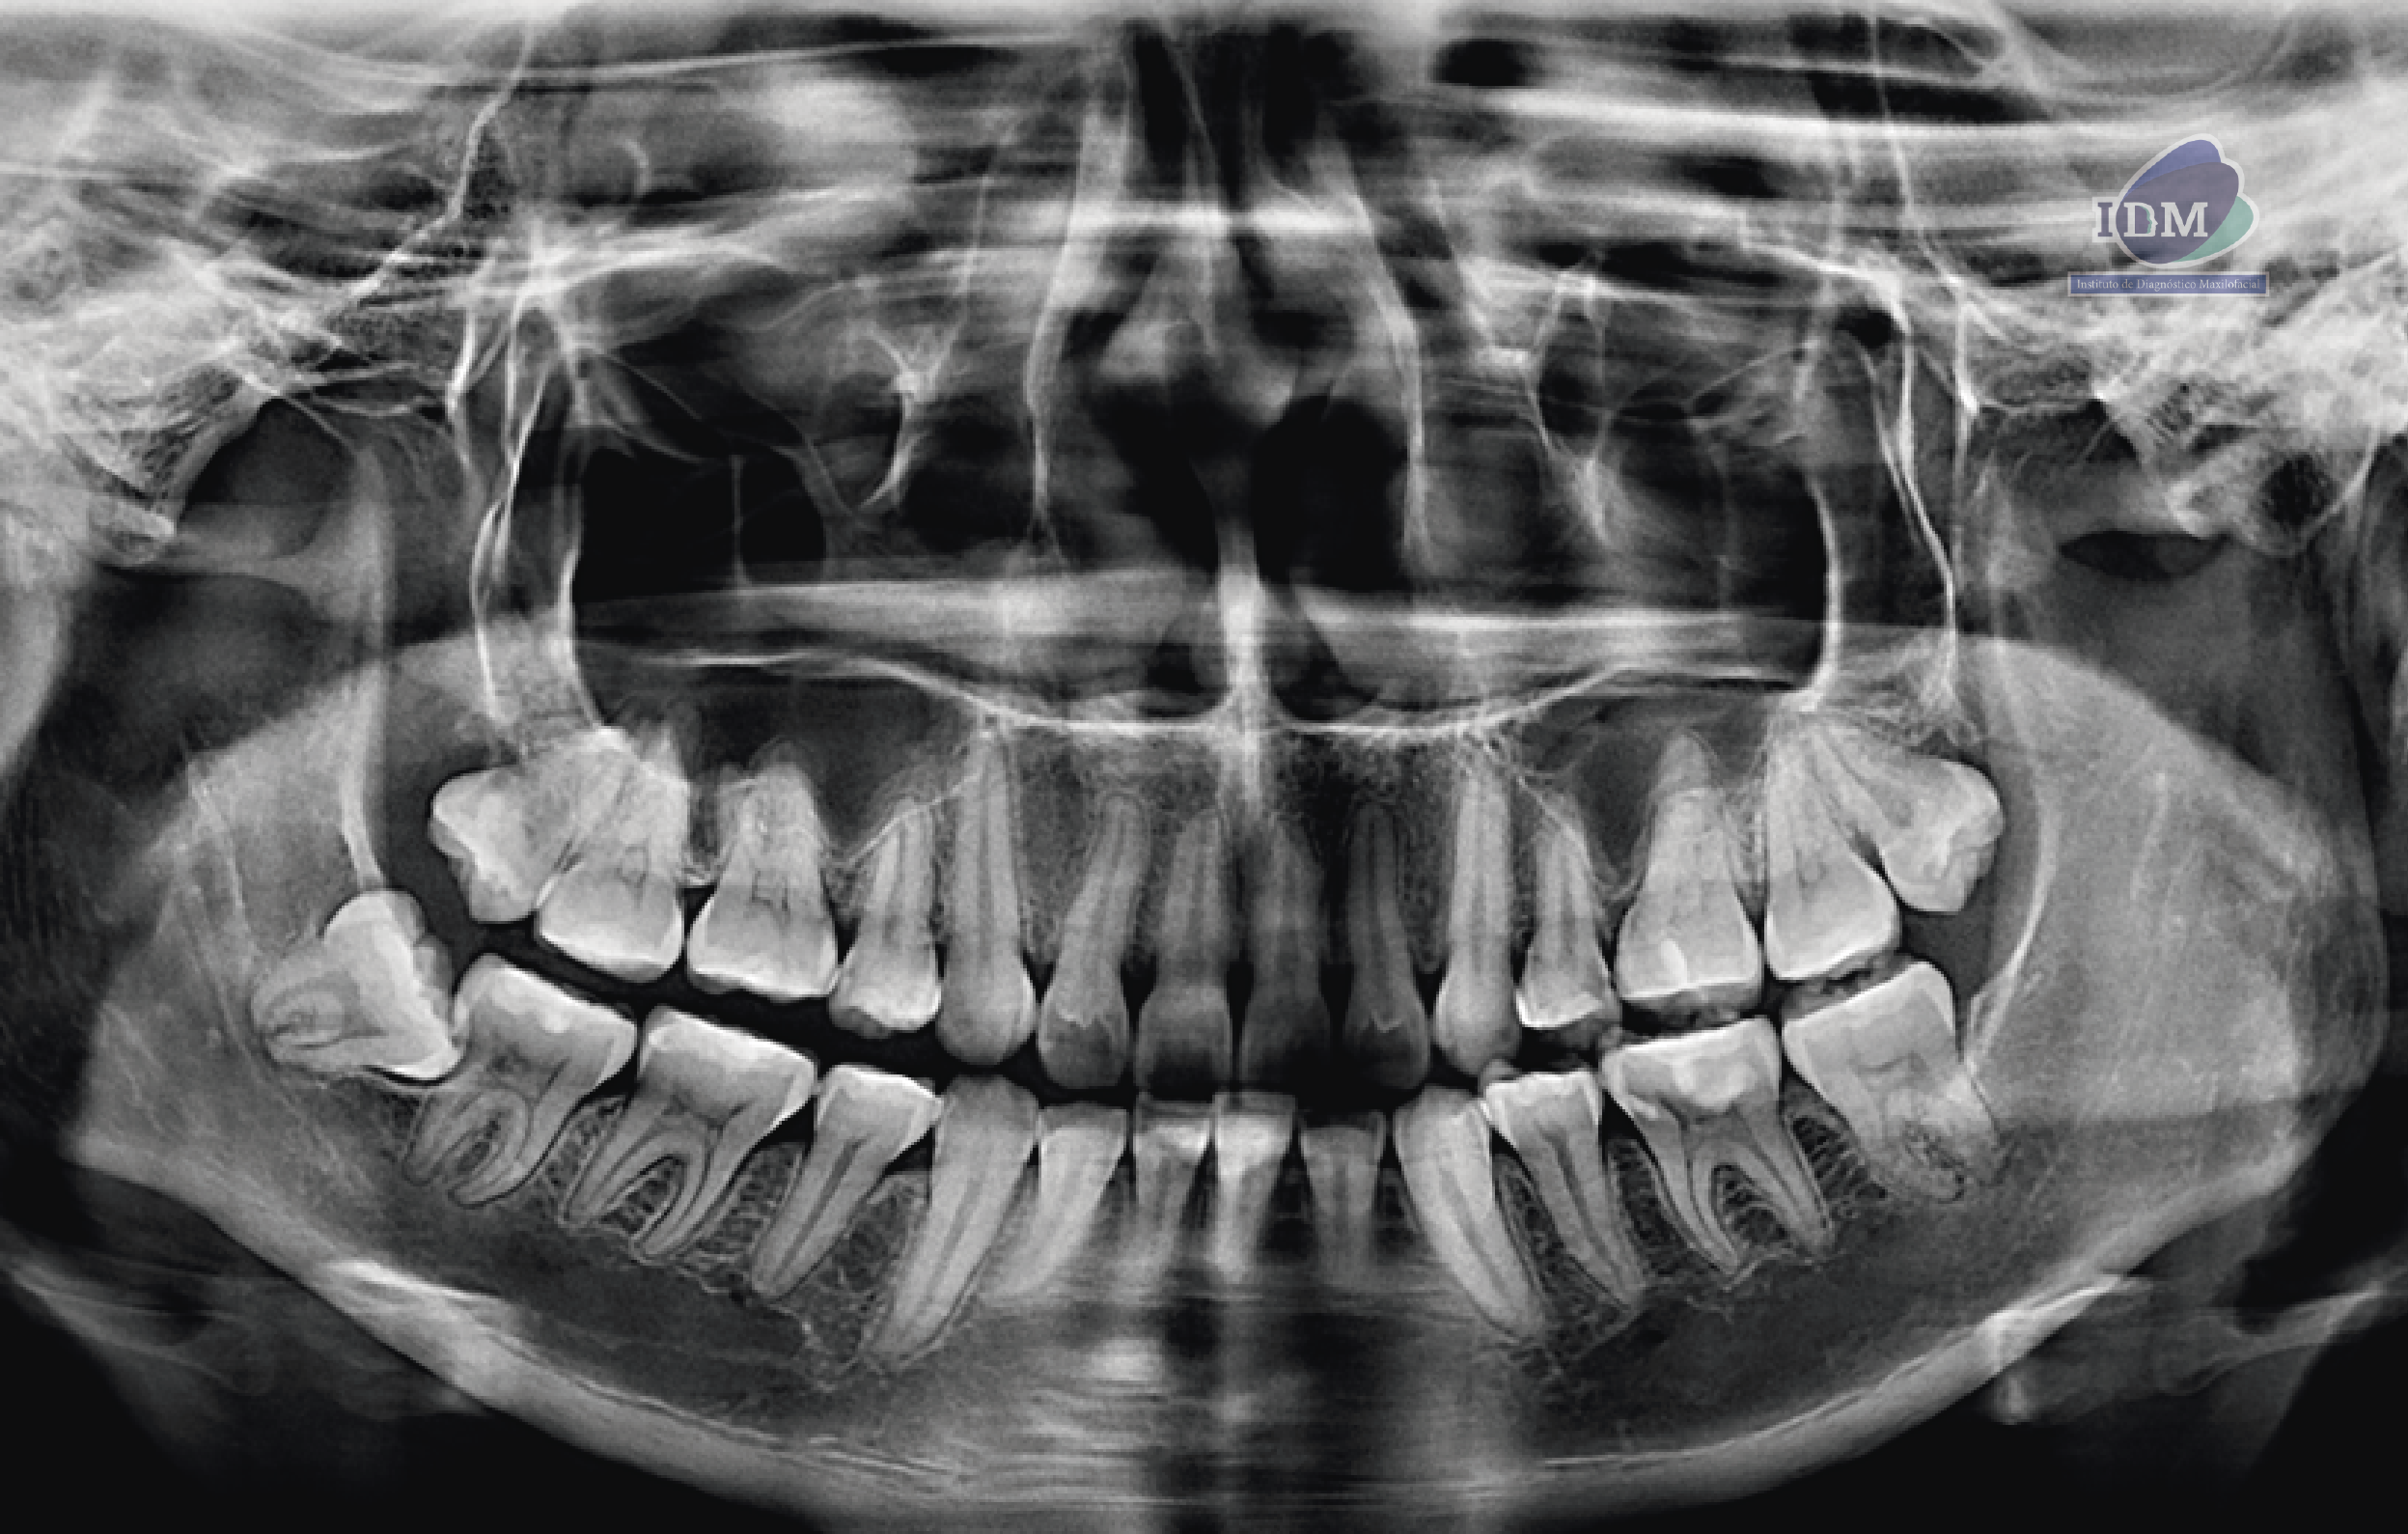

Paciente femenina de 20 años acude al centro para una evaluación imagenológica de ATM, a la evaluación de la radiografía panorámica se observa el aplanamiento del contorno condilar del lado derecho y la aparente alteración de la morfología condilar del lado izquierdo, asimismo se observa la neumatización de ambos senos maxilares a predominio del lado izquierdo, lesión cariosa distal

de la pieza 25, múltiples restauraciones coronarias y la impactación de la pieza 48.

Radiografia Panorámica

Los principales signos hallados por medio del diagnóstico por imágenes son: esclerosis del hueso subcondral, erosión, aplanamiento de las superficies articulares, deformación en la superficie condilar, osteofitos y disminución del espacio articular 9,32,50 . La radiografía panorámica, es la primera herramienta para identificar cambios estructurales a nivel de la ATM; sin embargo, la agudeza con la que puede evidenciar estos cambios debe ser evaluada con Cuidado.